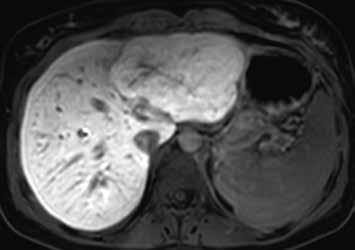

Nativně na CT je nezřetelně naznačeno několik hypodenzních ložisek (17). Všechna se vcelku homogenně sytí v arteriální fázi (18). V portovenózní fázi je sycení jater celkově nehomogenní, ložiska jsou však nadále lehce hyperdenzní oproti okolnímu parenchymu jater (19).